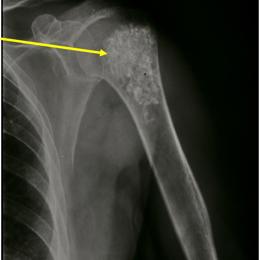

Radiographic imaging is used to help form a diagnosis. These include X-Ray, MRI, CT and Bone Scans.

An example of an enchondroma X-Ray is shown.

The empty bone cavity is usually filled with bone graft or bone cement. Bone can be donated (allograft) or taken from the patient themselves (autograft). Fixation devices, such as a plate and screws, may be used in specific situations to prevent postoperative fracture. This example of an X-ray shows the bone graft filled in nicely. It looks particulate. In this case, the patient was placed in a cast to protect from fracture and allow the graft to heal.